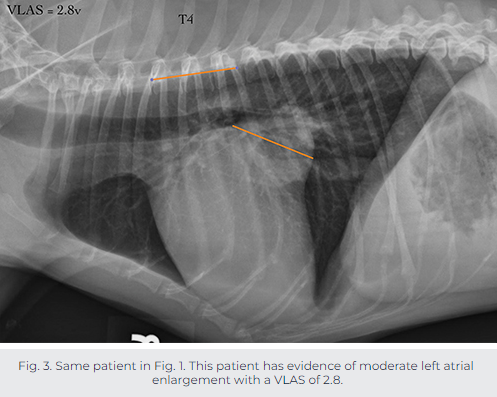

실측정 예시는 다음과 같다.

이번에 나온 논문은 전통적인 심장 크기 평가인 VHS와 VLAS 간에 어떤 것이 폐수종 예측에 적합한지에 대한 논문이다.

VLAS가 심부전 예측율이 더 높았고, 2.3일 때 민감도와 특이도가 매우 높은 것으로 측정하고 있다.